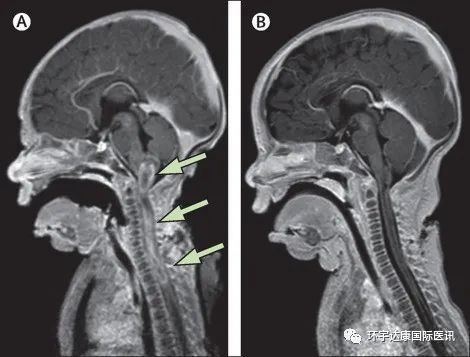

医生为婴儿做了全面的检查:头部超声没有显示异常。然而脑和脊柱的增强核磁显示髓内病变从延髓向下延伸到上胸段脊髓,这可能是高级别肿瘤!

就在接受了诱导化疗和低剂量 VITRAKVI(拉罗替尼)治疗后一周,这名婴儿的脊柱肿瘤就已经出现了肉眼可见的缩小;第二周,医生就加大了剂量,开始100 mg/m 2的全剂量进行治疗,这时病灶已经显着减小,她的四肢瘫痪也出现了明显改善。

令M女士难以置信的是,VITRAKVI(拉罗替尼)联合化疗治疗了8周后,肿瘤已完全消退,影像学显示已经没有任何病灶!